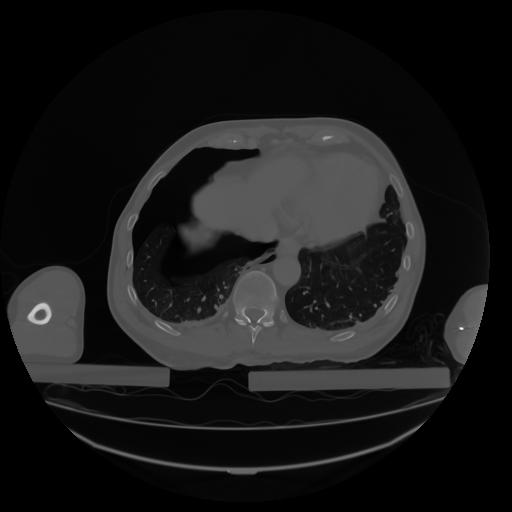

27 CUERPO,CE,Axial,3.0,CUERPO,,